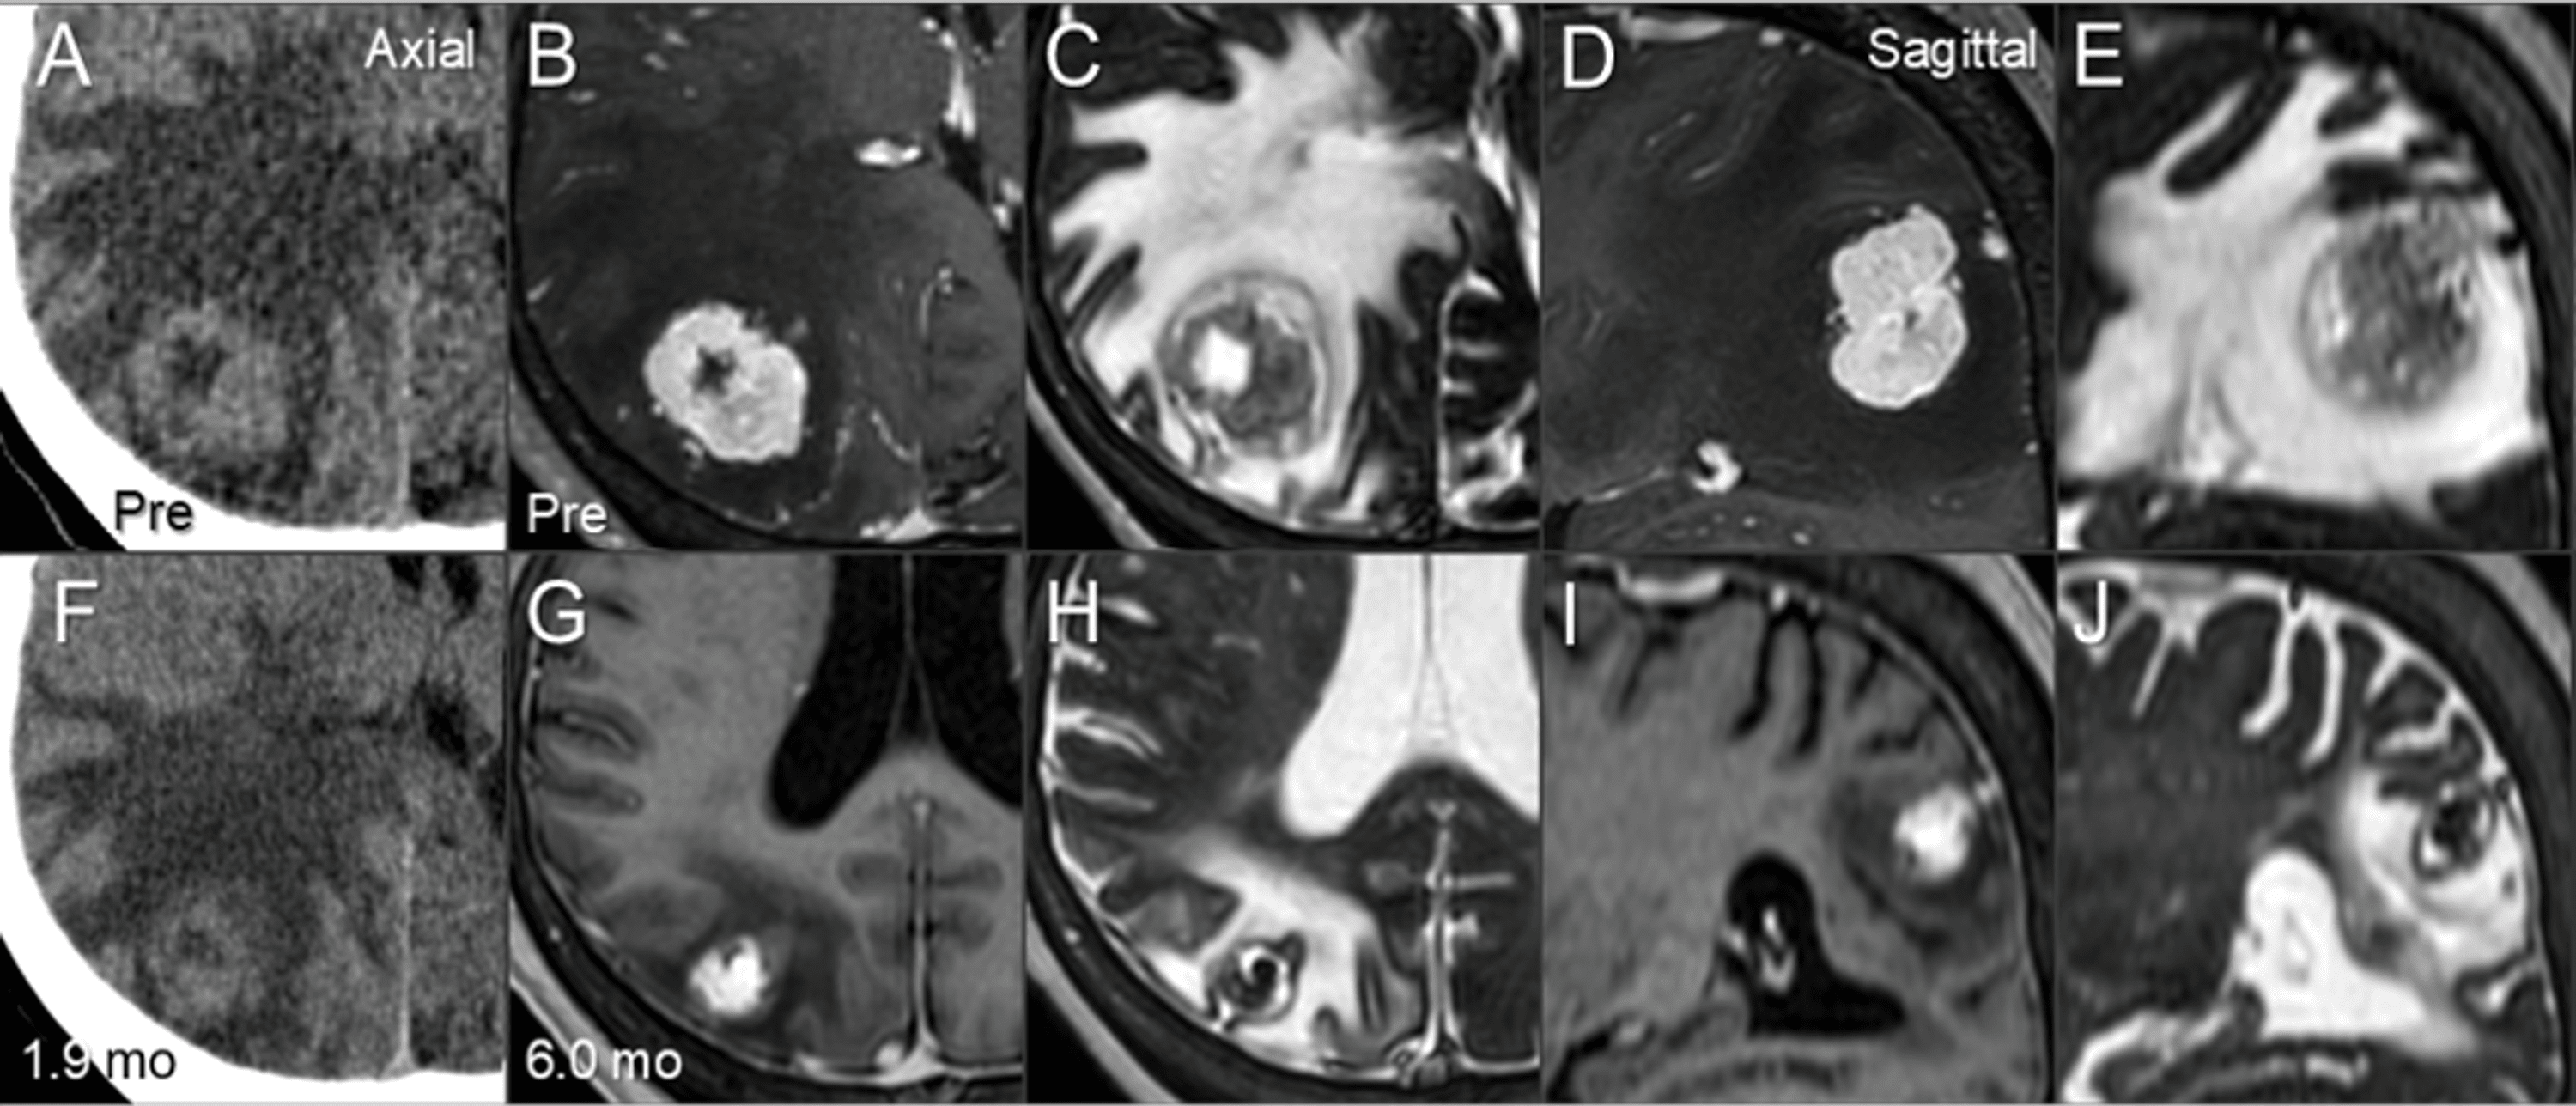

Cureus Gradual and Remarkable Tumor Shrinkage Following Seven Radiosurgery Protons For many patients, stereotactic radiosurgery (srs) offers a minimally invasive, curative option when surgical techniques are not. Web stereotactic radiosurgery (srs) was conceived by a team of neurosurgeons and physicists in sweden. Part i deals with the relevant physics and planning algorithms of protons (h breuer) and part ii with the radiobiology,. Web in preparing to use protons in radiosurgery. Radiosurgery Protons.